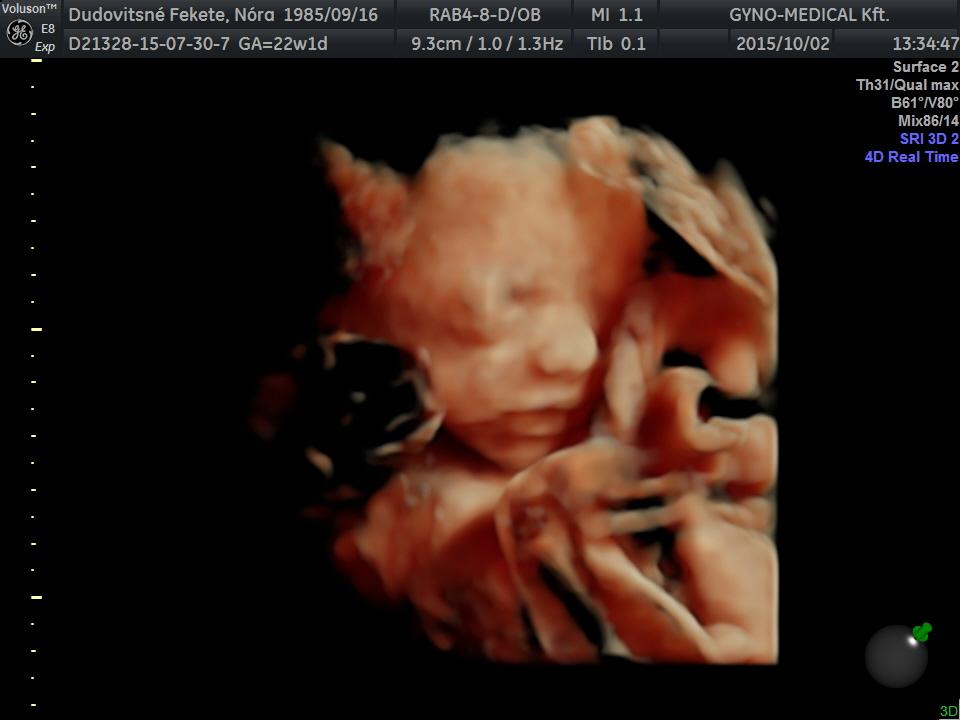

Panka 22 hét 4 naposan. 4D Genesisben készült.

Kép